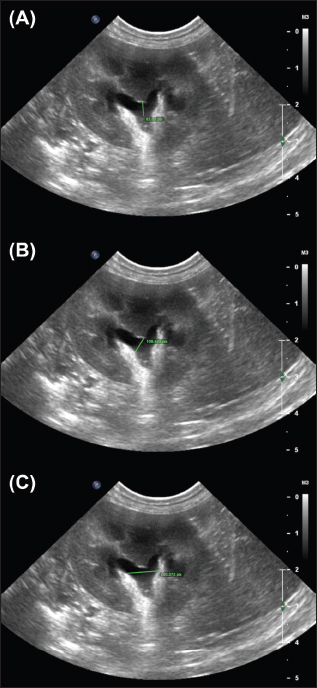

Supplementary 2. Examples of the ‘Transverse crest-to-ureter’ (TCU) (A), ‘Transverse pelvic width’ (TPW) (B), and ‘Transverse Dorsoventral’ (TDV) (C) measurements performed by observers.

Supplementary 3. Examples of the ‟Sagittal pelvic width” (SPW) (A), ‟Sagittal pelvic length (SPL)” (B), and ‟Sagittal Parenchymal Percentage” (SPP) (C) measurements performed by observers.